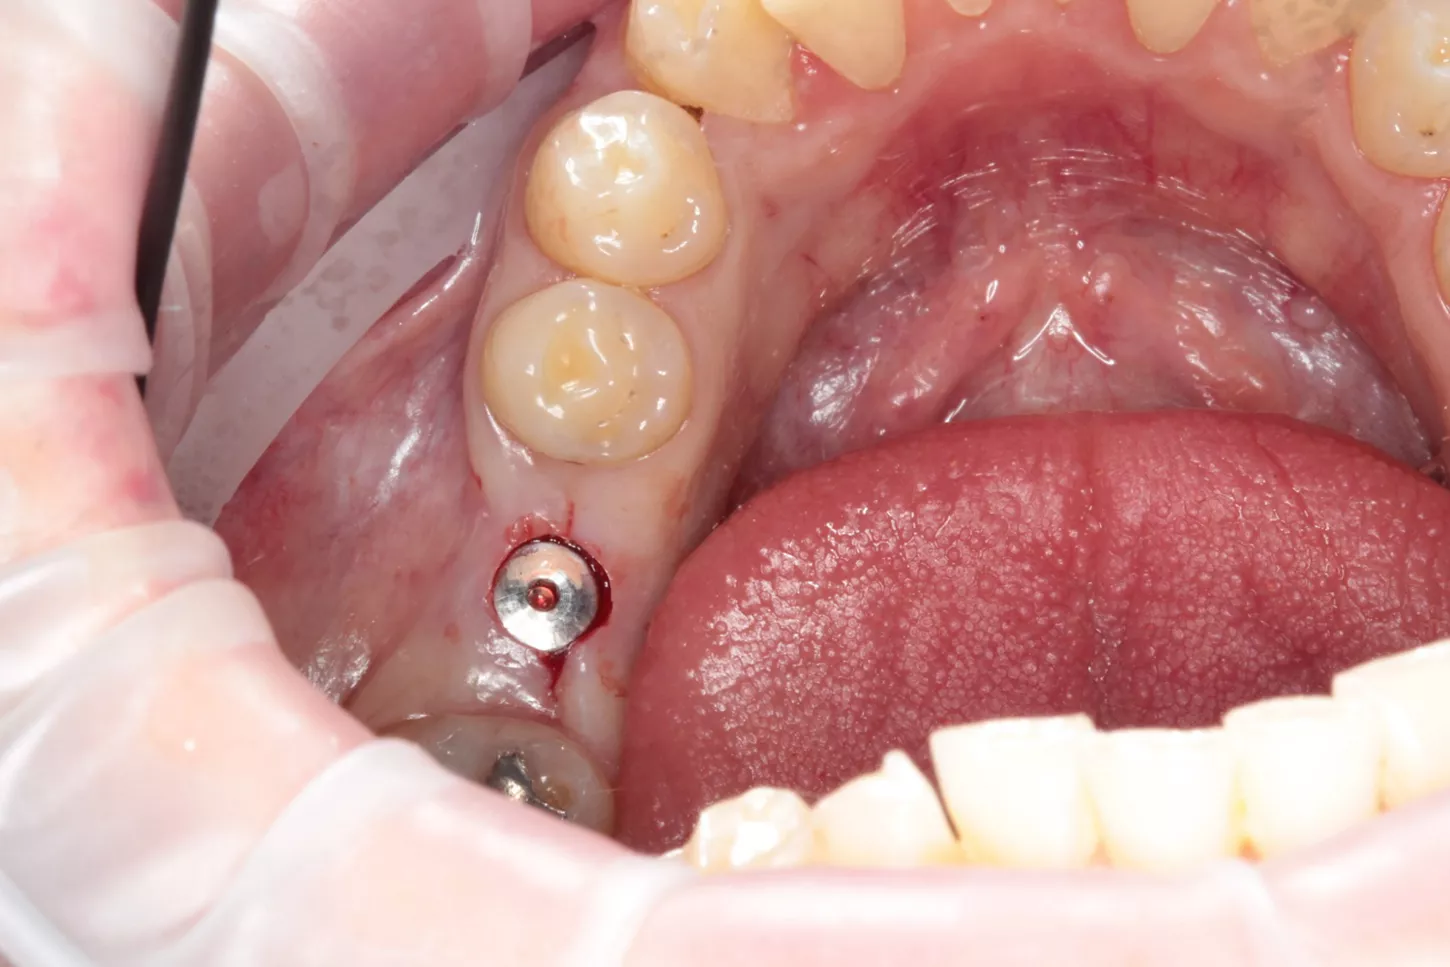

9a. 9b. 9c. Dans ce cas, en raison de la quantité suffisante d'os, j'ai pu utiliser l'approche sans lambeau avec le tissue punch.

10. Ensuite, j'ai suivi le protocole de forage Anthogyr Axiom X3® pour l'os de type 2 (sous-préparation  d'un foret). L'implant a été placé à travers le guide. Le couple a atteint 50 N.cm. L'ensemble de la procédure nous a pris environ 20 minutes !

11. La vis de couverture doit être serrée à la main.